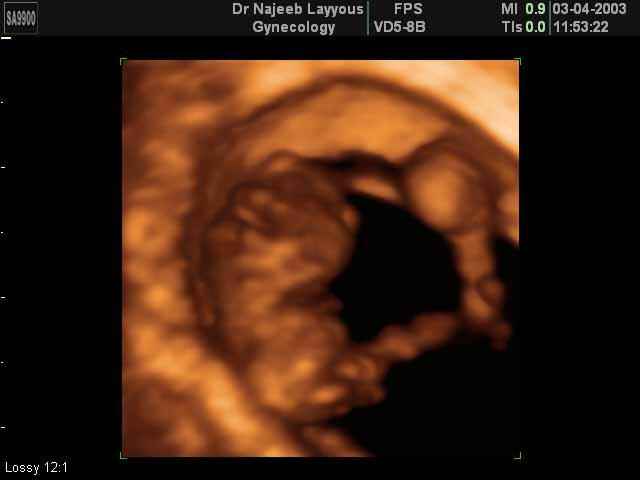

3D First Trimester Ultrasound Scan Photos ( Early Pregnancy Ultrasound Photos ) | Dr N Layyous

3D First Trimester Ultrasound Scan Photos